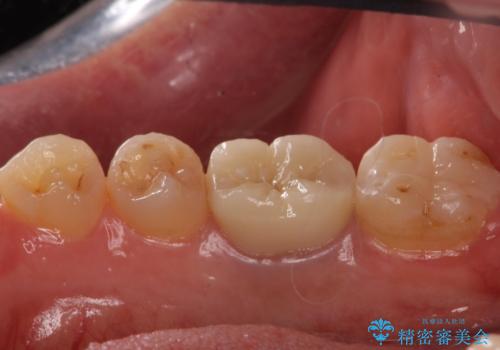

- 右下6 精密根管治療(大臼歯・リトリートメント):143,000円 土台:22,000円 仮歯:11,000円 ジルコニアクラウン:121,000円 合計297,000円費用は治療当時の料金となります

治療後は症状も改善し、半年後の経過も良好です。